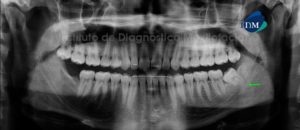

Paciente de sexo femenino de 32 años de edad acude al Instituto de Diagnóstico Maxilofacial para evaluación general de ambos maxilares. A la evaluación panorámica